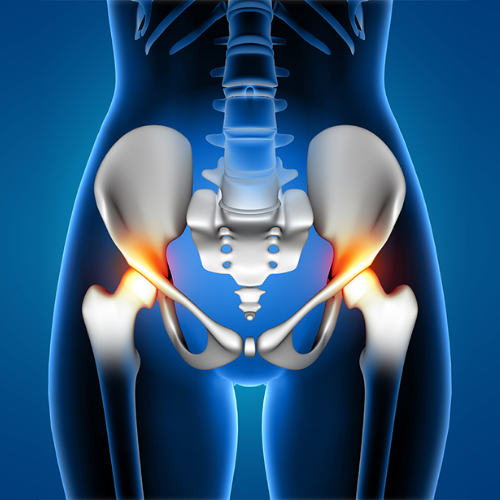

Hip pain can arise from a range of causes including overuse, arthritis, trauma, or tendon and muscle injuries. Because the hip joint supports most of your body’s weight, even minor issues can lead to persistent discomfort and stiffness. At REGENIQUE, we focus on understanding the exact cause of your hip pain—whether it's from the joint, surrounding soft tissues, or referred nerve pain—so your treatment is accurate and effective.

Conditions We Treat

Hip Arthritis

Avn - Avascular Necrosis Hip

Ischial Bursitis

Adductor Tendinopathy